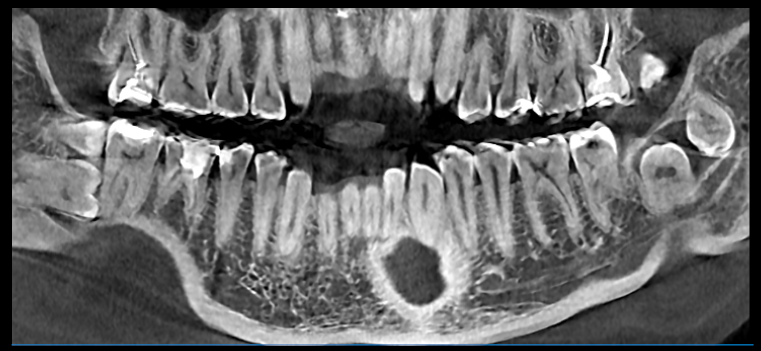

Вот такие коварные восьмые, а иногда и девятые маляры залегают в толщи кости.

Как происходит процесс удаления зуба мудрости? В первую очередь перед процедурой наш дантист сделает рентген, чтобы определить местоположение и особенности строения зуба. Сама операция проходит под местной анестезией, и мы Вас уверяем что Вы даже не почувствуете укола. При прорезовшемся зубе после действия обезболивающего врач при помощи специальных инструментов извлечет зуб и наложит швы. Длится такая операция несколько минут , но стоит заметить, что верхние восьмерки как правило удаляются быстрее, потому что у нижних зубов корни имеют менее крепкую и извилистую структуру.

У пациентов, помимо прорезыванных зубов мудрости, встречаются и так называемые ретинированные, это те которые полностью скрыты под десной, а также дистопированные - с неправильным расположением в зубном ряду. Чаще всего встречаются ретенированные и дистопированные зубы одновременно. Следует также выделить полуретинированные восьмерки - это зубы , которые появились из десны не до конца. Зачастую в том варианте, когда видна только часть зуба, между ним и десной образуется небольшой карман- капюшон, и это образование вызывает гнойное воспаление - перикоронит. В запущенных случаях, помимо болевых ощущений в самой зоне зуба перикоронит может вызывать сильнейшие головные боли и повышение температуры.

Протезирование на имплантантах

В

задней области верхней челюсти, замена зуба с

помощью зубных имплантатов, зачастую, требует хирургической операции по пазухе.

Эта операция представляет собой форму предварительной протезной

хирургии для повышения качества и количества кости в задней области

верхней челюсти. Предварительная оценка верхней челюсти необходима для успеха этой операции.

Если количество костей, между гребнем и полостью, является недостаточным, (<5 мм), то необходима процедура открытого синусового подъема ( синус лифтинг).

В представленном случае была сделана , как раз такая операция на верхней челюсти перед установкой имплантов.